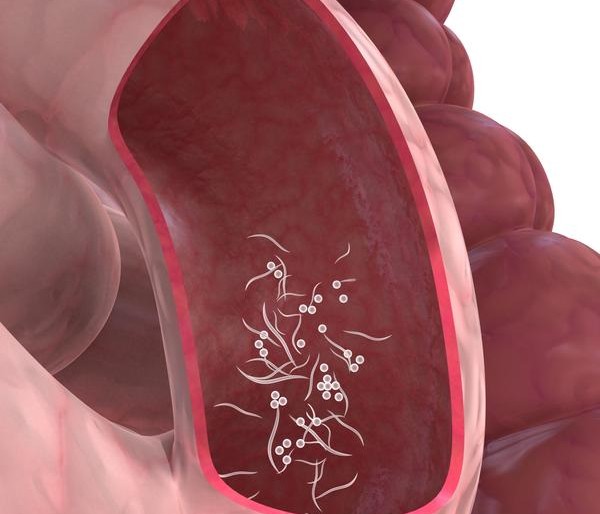

Известно несколько видов остриц. В теле индивида паразитирует Enterobius vermicularis. Довольно часто эти гельминты атакуют малышей. Детская привычка грызть ногти, брать в рот пальцы в разы увеличивает риск заражения, которое не связано с расой, социальным статусом, полом или культурой. Паразитируют острицы в отделах толстого и тонкого кишечника.

На переднем конце тела паразита расположена везикула, которая окружает ротовое отверстие и служит приспособлением для крепления к кишечнику. Взрослая особь острицы имеет длину от 8 до 13 мм, ее задняя часть заострена, а толщина не более 0,5 мм. Самец немного короче, его длина около 3 мм. Задняя часть у него волнистая. Матка у самок растянута, а когда она заполнена яйцами, то заполняет всю поверхность тела. Как выглядят яйца остриц? Они прозрачные, бесцветные, асимметричные и снабжены тонкой оболочкой. Внутри яйца находится личинка, обладающая сероватым оттенком. Прозрачность и очень малый размер делают их незаметными для невооруженного глаза. Развитие, оплодотворение и рост осуществляется в тонком кишечнике, именно там имеются благоприятные для этих процессов условия. Далее гельминт перемещается в слепую кишку и толстый кишечник, в котором обитает до гибели.

Цикл развития паразита от 14 до 21 дня. В некоторых случаях он увеличивается до 30. Начинается он с момента проглатывания яиц глистов. За этот период женские особи откладывают тысячи яиц. Самки живут до 13 недель, а самцы – в два раза меньше. После спаривания мужские особи сразу погибают. Самки, прикрепившись к слизистой оболочке кишечника, питаются его содержимым. В теле женской особи может находиться до 16 тысяч яиц, т. е. все ее тело практически заполнено ими. В результате самки теряют способность к фиксации и спускаются ниже по толстой кишке. Движение их происходит во влажной среде. В период сна человека самки выползают наружу через анальное отверстие. Стимулирует кладку яиц сухость дермы. После этого особь возвращается в толстый отдел кишечника и погибает. Ползание паразитов вызывает зуд. При расчесывании этих участков кожи яйца легко приникают под ногтевую пластину и могут попасть в ротовую полость. Таким образом, несмотря на короткий период жизни гельминтов, индивид способен болеть длительное время. Энтеробиоз считается трудноизлечимым заболеванием.

У женщин яйца остриц (как выглядят, видно на фото ниже) могут проникнуть во влагалище. В этом случае возникает воспаление и раздражение его слизистых оболочек. Признаки, которые указывают на наличие гельминтов в женских половых органах:

Микроскопический размер яиц позволяет рассмотреть их только под сильным увеличением. Как выглядят яйца остриц под микроскопом? Фото ниже даст ответ на этот вопрос. Лаборант, исследуя биоматериал, наблюдает следующую картину. Форма яйца овальная, причем одна сторона более выпуклая. Внутри находится вытянутая личинка. Оболочка яйца состоит из двух контуров и полностью бесцветна.